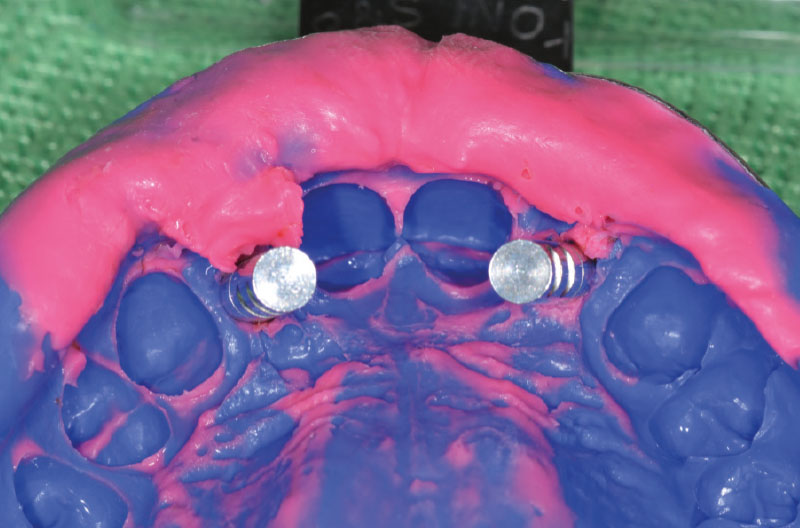

Per la presa dell’impronta si avvitano dei transfer Pick-up su entrambi gli ExaConnect (Fig. 30).

L’impronta viene inviata al laboratorio odontotecnico che avvita gli analoghi ExaConnect ai transfer Pick-up per la realizzazione di un modello in gesso e confeziona dei provvisori su monconi Ti-Base per ExaConnect (Figg. 31-35).